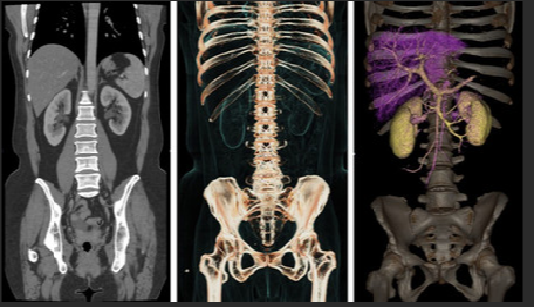

A reconstrução tridimensional (3D) é uma técnica avançada que transforma os cortes axiais obtidos durante a Tomografia Computadorizada (TC) em imagens volumétricas, permitindo uma visualização muito mais rica das estruturas anatômicas. Essa visualização pode ser manipulada em diversos ângulos, facilitando a interpretação por parte do médico radiologista e contribuindo para condutas clínicas e cirúrgicas mais seguras.

💻 Tipos de reconstruções disponíveis:

- MPR (Multiplanar Reconstruction): Visualização em planos axial, sagital e coronal

- MIP (Maximum Intensity Projection): Destaque para estruturas hiperdensas, como vasos

- VR (Volume Rendering): Reconstrução volumétrica realista, ideal para face, coluna e extremidades

- SSD (Shaded Surface Display): Superfície sombreada, usada em ortopedia e crânio